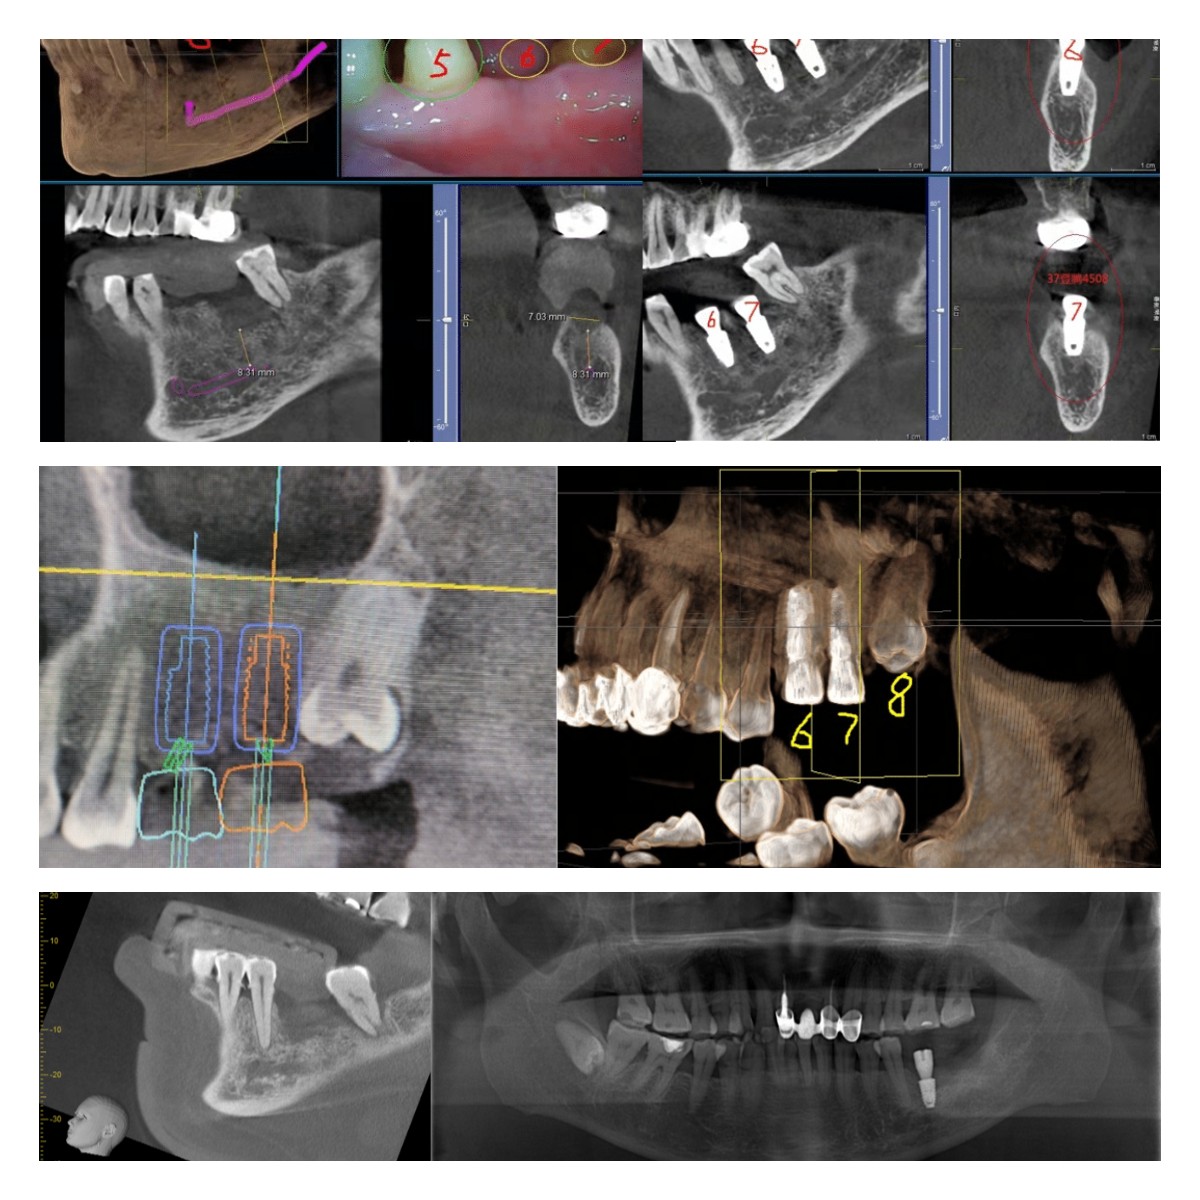

部分病例展示: